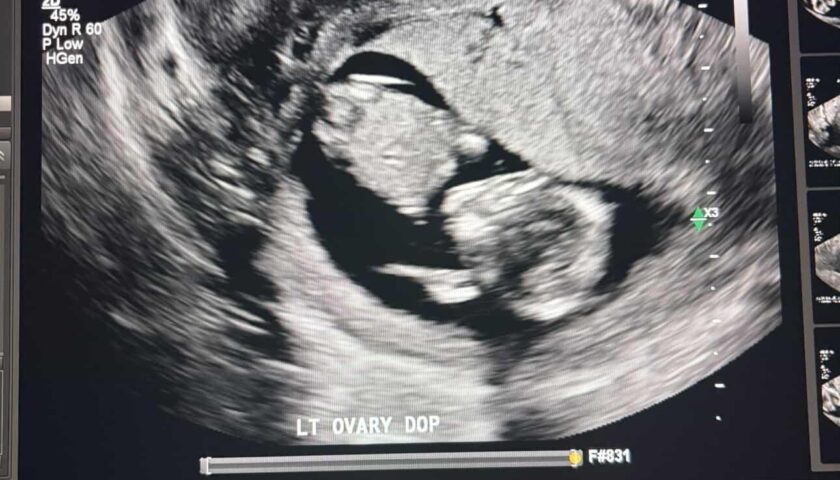

Week 21

Week 21 out of 40 of Pregnancy!

We got to see baby again! The anatomy scan was fun for mom and dad, but the technician had a hard time getting good photos of baby because baby kept jumping around! Baby is measuring “perfectly” and has both arms and legs, and a healthy heartbeat.